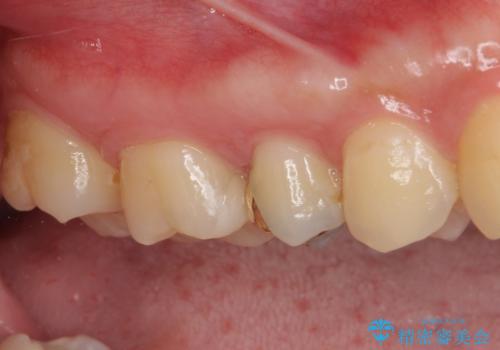

- 奥歯の銀歯の下にあるむし歯治療を希望して来院された患者様です。

口を開けたときに見えてしまう部分はセラミックインレーやジルコニアクラウンに、目立たない部分はゴールドインレーにてむし歯治療を行うこととしました。

機能面を優先すると、PGAインレー(ゴールドインレー)による修復治療やPGAクラウンによる補綴治療が望ましいのですが、笑ったときに見えている銀歯がどうしても気なってしまうとのことで、目立ってしまう奥歯はセラミックインレーやセラミッククラウンを装着することとしました。

見た目を気にすることなくむし歯治療を行うことができ、患者様に大変満足していただきました。